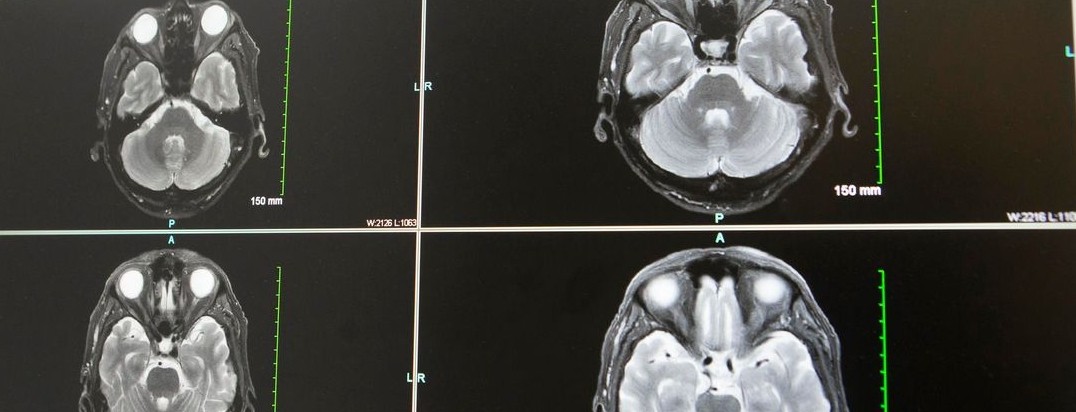

Featured photo at top of brain scans. Photo courtesy of Joseph Broderick.